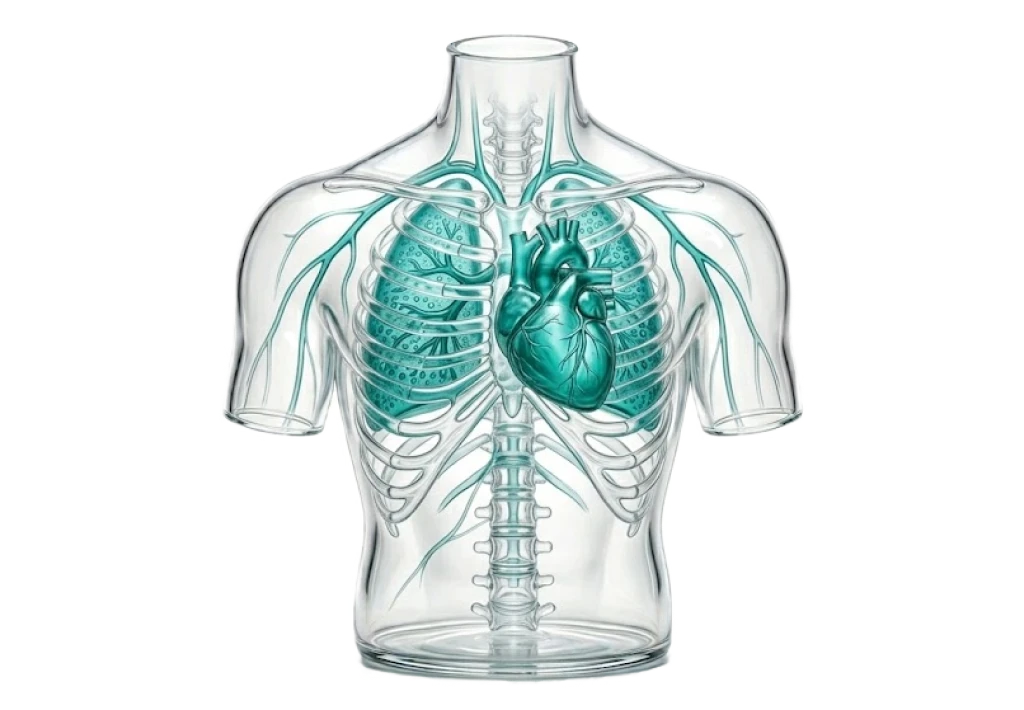

Кардиология

қызметтер: 4